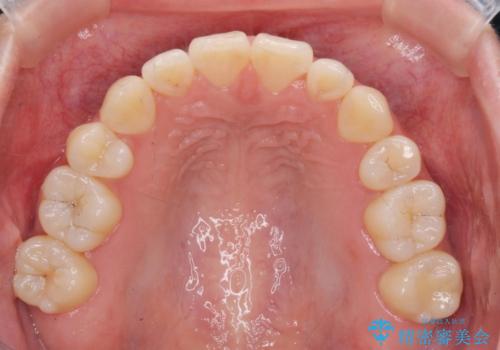

マウスピースで行う出っ歯の改善 後方移動

少し時間はかかりましたが、しっかりと綺麗な歯並びに仕上げることができ、大変喜んでいただくことができました。